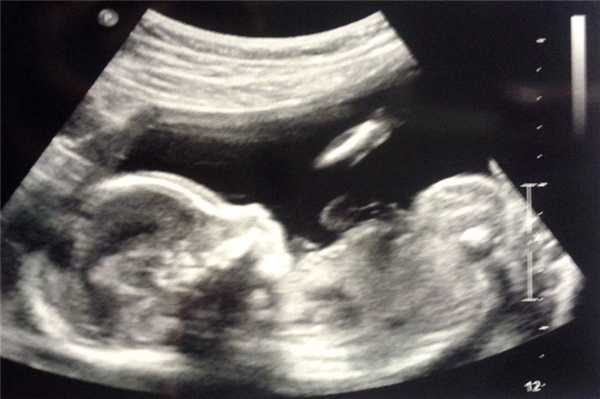

Фото УЗИ ребенка на разных сроках беременности

Если беременность желанная, будущие родители внимательно относятся к пренатальной диагностике плода. Чтобы убедится, что ребенок развивается нормально, в течение 9 месяцев гинеколог несколько раз направляет женщину на ультразвуковое исследование. Фото УЗИ может многое рассказать врачу и будущим родителям о малыше. Кроме того, снимок станет трогательным напоминанием для семейного архива.

Что показывает фото ультразвукового исследования по неделям беременности?

В зависимости от срока, на фото определяются разные параметры и особенности развития малыша. Рассмотрим, что же видно на снимках по акушерским неделям вынашивания.